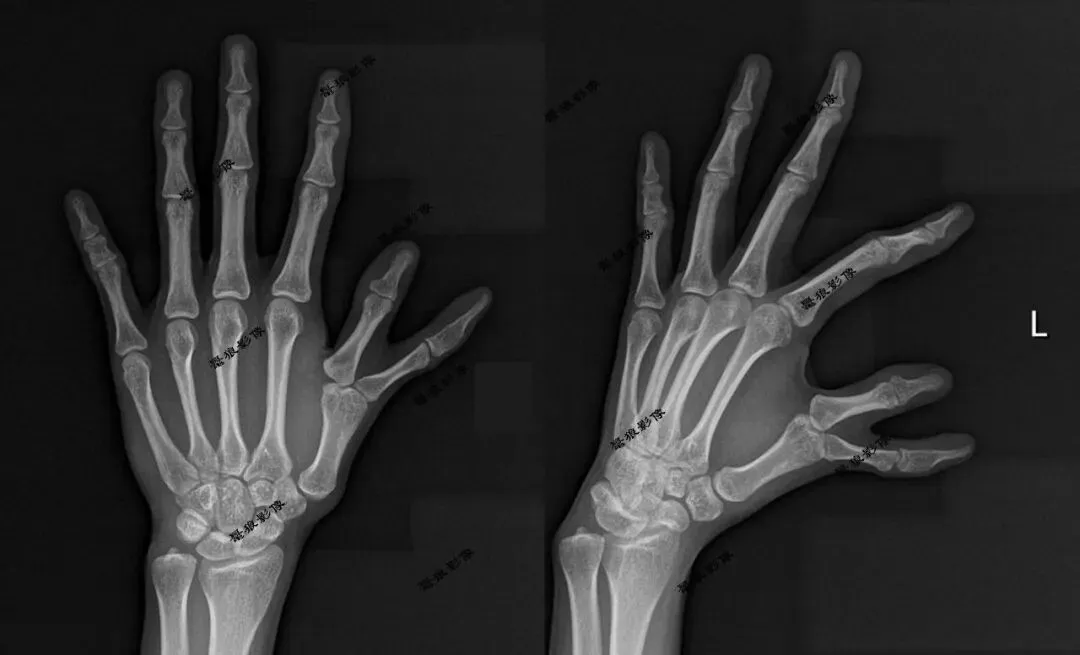

案例二:

案例二:术前